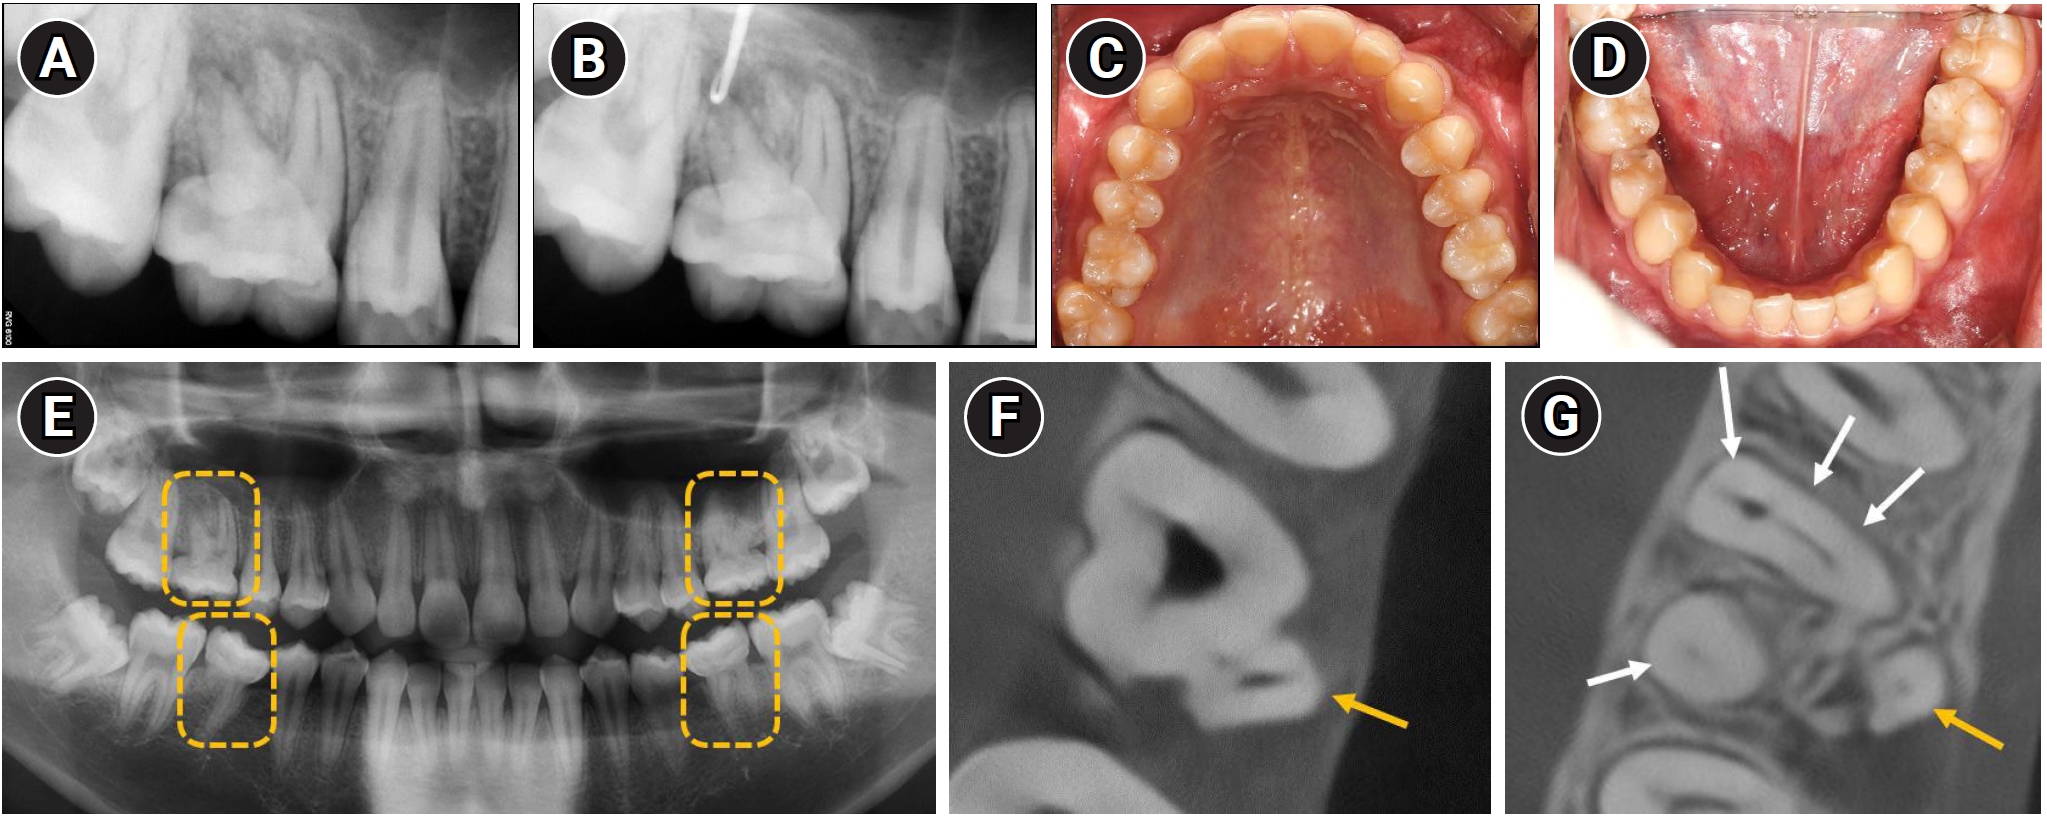

Diagnostic evaluation of maxillary right first molar and overall dentition. (A) Periapical radiograph showing an ill-defined radiolucency associated with tooth #16. (B) Radiograph confirming communication of the sinus tract with the periapical area. (C, D) Intraoral photographs showing normal coronal morphology of all first molars. (E) Panoramic radiograph revealing that all first molars have shortened, tapered roots. Yellow dashed boxes highlight the affected maxillary and mandibular first molars on both sides. (F) Cone-beam computed tomography (CBCT) axial view demonstrating that the palatal canal (yellow arrow) is not in continuity with the pulp chamber. (G) CBCT showing five root canals: three in the mesiobuccal root, and one each in the distobuccal (four white arrows) and palatal roots (yellow arrow).

Although the coronal morphology of all four first molars was normal (Figure 1C and D), all exhibited root malformations (Figure 1E), leading to a diagnosis of MIM. Based on clinical and radiographic findings, the maxillary right first molar (#16) was diagnosed with pulp necrosis and chronic apical abscess, and nonsurgical root canal treatment was planned.

To obtain a more accurate assessment of the root canal morphology, cone-beam computed tomography (CBCT) was performed. The palatal canal was found to be separated from the main pulp chamber (Figure 1F). Three canals were identified in the mesiobuccal root, and one canal each in the distobuccal and palatal roots, totaling five canals (Figure 1G).